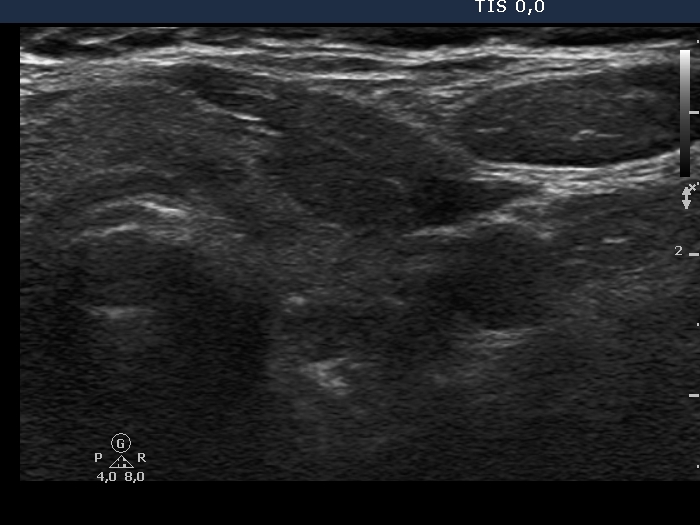

Examination in 2020 (third row of images):

Comment. This story draws attention to how important it may be to be aware of the results of a previous study. By result I do not mean the findings, but the archived recordings.Clinical data: The patient came to a routine follow-up. She had no complaints.

Palpation: Both lobes were a bit firm on palpation. There was a not firm nodule in the right lobe.

Laboratory test: TSH 3.38 mIU/L on daily 125 microgram levothyroxine.

Ultrasonography. The previously cystic lesion has spontaneously decreased in size, the cystic fluid has disappeared. However, the hyperechogenic foci were still visible. If we had only seen this current study, we would have had to regard these echogenic granules microcalcifications.

We recommended that she takes the replacement therapy at the same dose and has a TSH scan after a year and an ultrasound scan after three years.